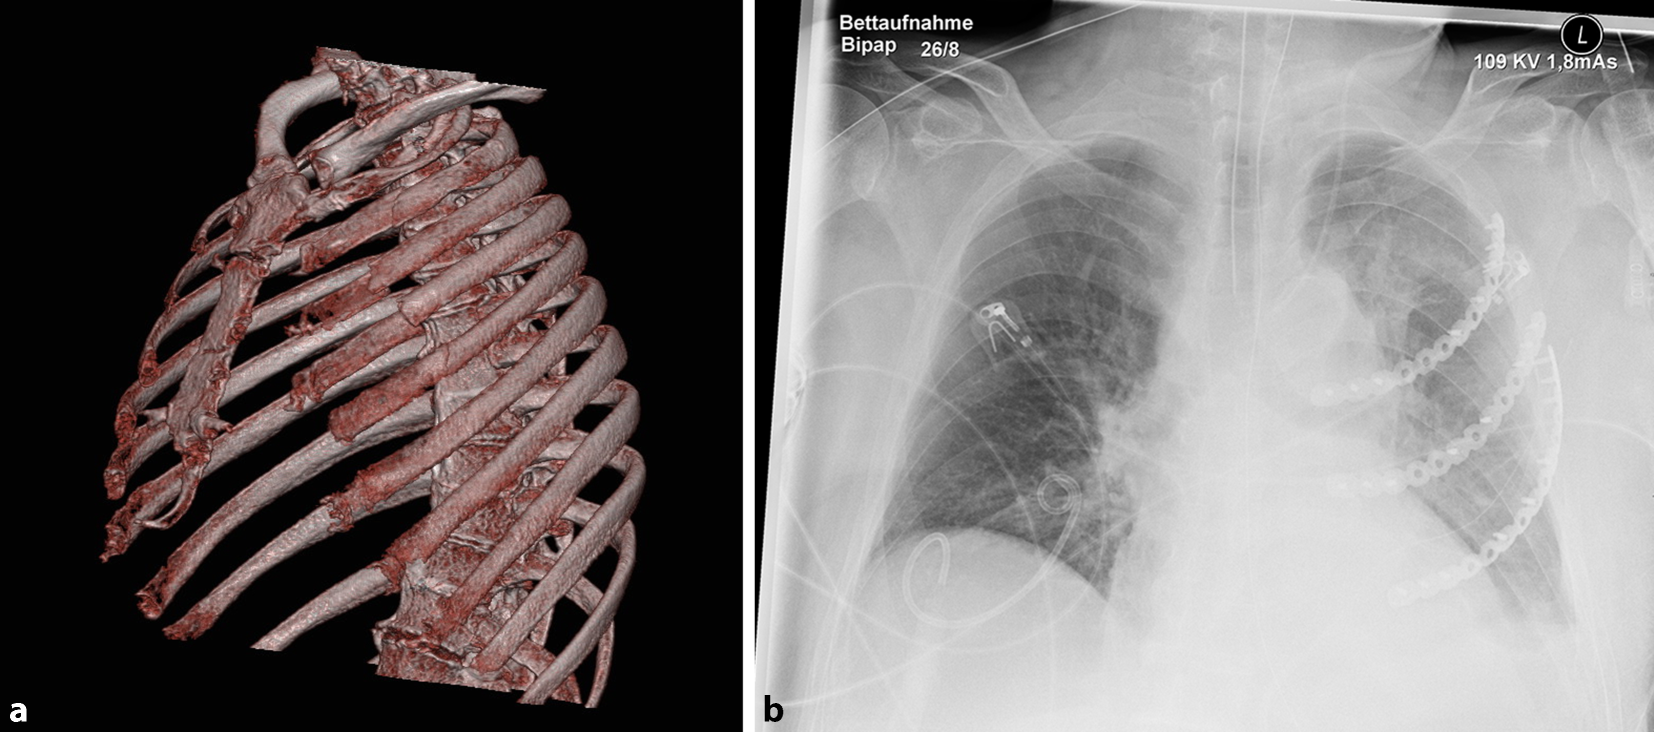

Durch die mehrfache Reanimation zog sich der Patient eine Sternumfraktur, Mehrfragmentfrakturen der 3. bis 5. Rippe sowie eine einfache Fraktur der 2., 6. und 7. Rippe links zu. Außerdem zeigten sich nichtdislozierte Rippenserienfrakturen 2–5 rechts (Abb. 1). In der Projektionsradiographie und in angeschnittenen Lungenanteilen im Abdomen-CT (Computertomograph) zeigte sich eine links basal führende Pneumonie mit erheblicher Sekretretention. Es bestand ein moderates ARDS (Acute Respiratory Distress Syndrome) mit Horowitz-Indizes zwischen 100 und 150 mmHg unter druckkontrollierter Beatmung mit Möglichkeit zu druckunterstützter Spontanatmung. Die Decarboxylierung war unter lungenprotektiven Beatmungsparametern ungestört.

Abb. 1

Darstellung des Thorax. a In „Volume-rendering“-Technik präoperativ, b postoperativer Röntgenbefund

Zum Indikationszeitpunkt (10 Tage nach erstmaliger Reanimation) blieben Spontanatmungsversuche allerdings frustran. Es zeigte sich klinisch ein zentraler instabiler Thorax mit inverser Atmung (Zusatzmaterial online: Video 1) und Sauerstoffpartialdrücken von 60 mm Hg bei einer FIO2 von 55 %. Weiterhin zeigten sich steigende Infektparameter und in der radiologischen Bildgebung (Abb. 1) eine Pneumonie mit linksbetonten Dystelektasen. Daher wurde am 10. Tag die Indikation zur Plattenosteosynthese der Rippen gestellt.